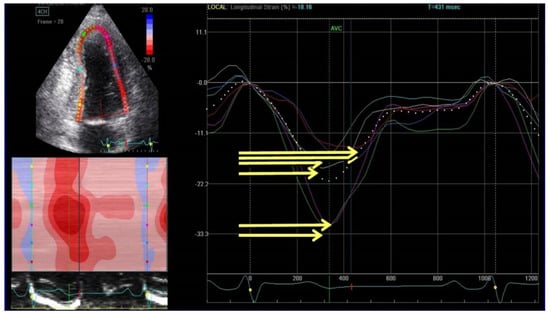

Speckle-tracking echocardiography (STE) allows for the measurement of the different components of active myocardial deformation (strain), providing an indirect evaluation of systolic function and presence of scar/fibrosis [33,34] (Figure 2).

Not only GLS but also mechanical dispersion, defined as the standard deviation of time to peak negative strain from the 16 segments of the left ventricle (Figure 3), was associated to arrhythmic risk in both ischemic and non-ischemic HFrEF [37,38].

Figure 2. Speckle tracking echocardiography evaluation in patients with previous inferior myocardial infarction notes a reduction of strain value in medium and basal segments of inferior and posterolateral walls (yellow line).

Figure 3. Evaluation of mechanical dispersion by speckle tracking echocardiography. Mechanical dispersion is calculated as the standard deviation of time to peak regional negative strain (yellow lines).